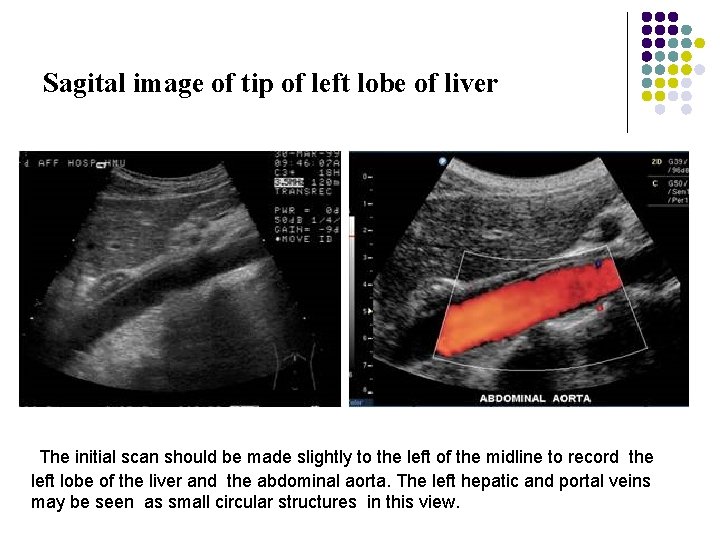

Longitudinal Scan Plane l Scan Ⅰ The initial scan should be made slightly to the left of the midline to record the left lobe of the liver and the abdominal aorta. The left hepatic and portal veins may be seen as small circular structures in this view.

Sagital image of tip of left lobe of liver The initial scan should be made slightly to the left of the midline to record the left lobe of the liver and the abdominal aorta. The left hepatic and portal veins may be seen as small circular structures in this view.